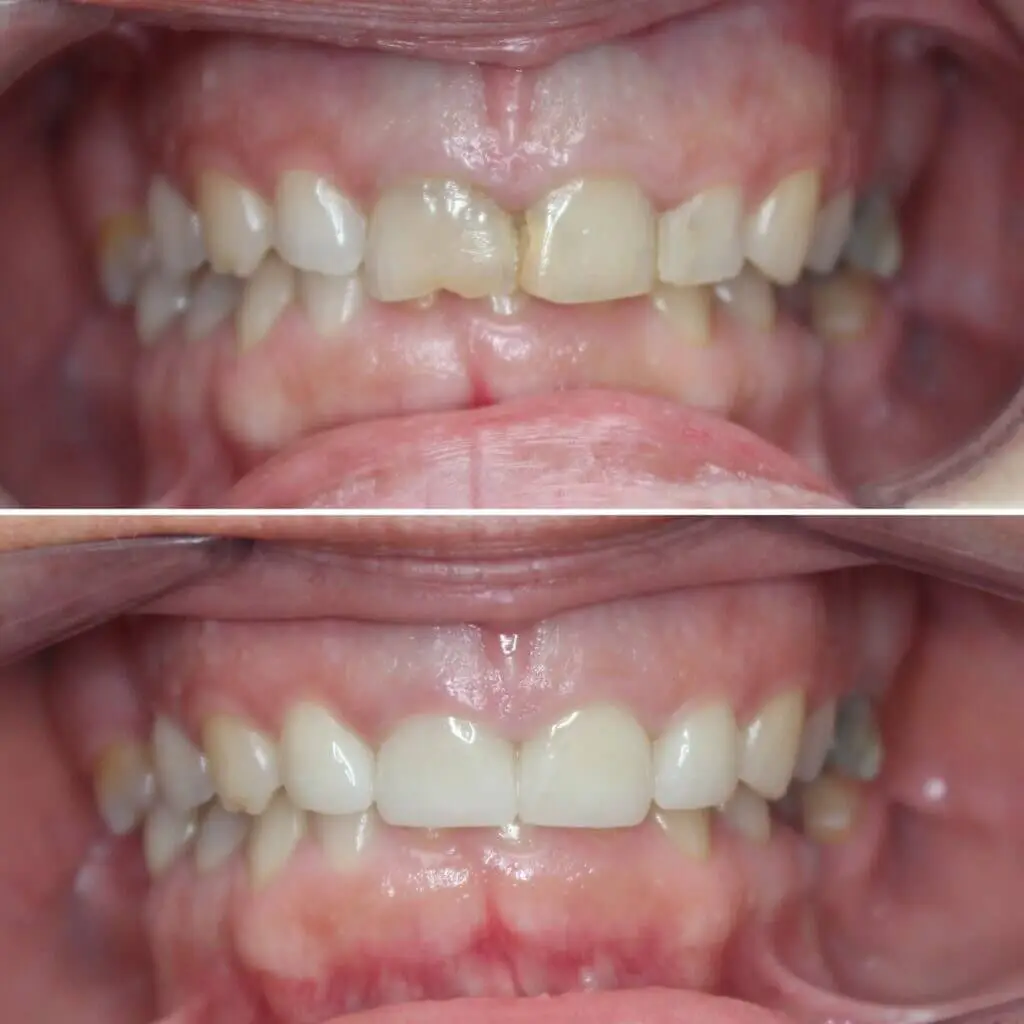

Fogszabályozás

Fiatal páciensünk elülső nyitott harapásának kezelésére első lépésként belső fogszabályozó készüléket kapott, melynek funkciója a felső fogív tágítása, felső nagyőrlők mozgatása.

A következő lépés a rögzített készülék felragasztása volt alsó és felső fogíven, eltérő időpontokban.

A kezelés kb. 2 évig tartott.